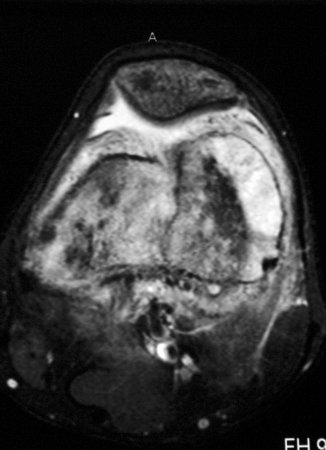

Osteossarcoma

Ressonância nuclear magnética (RNM), incidência axial; osteossarcoma do fêmur distal mostrando sinal de alta intensidade; imagem ponderada em T2

Do acervo do Dr. Michael J. Klein e da Dra. Luminita Rezeanu